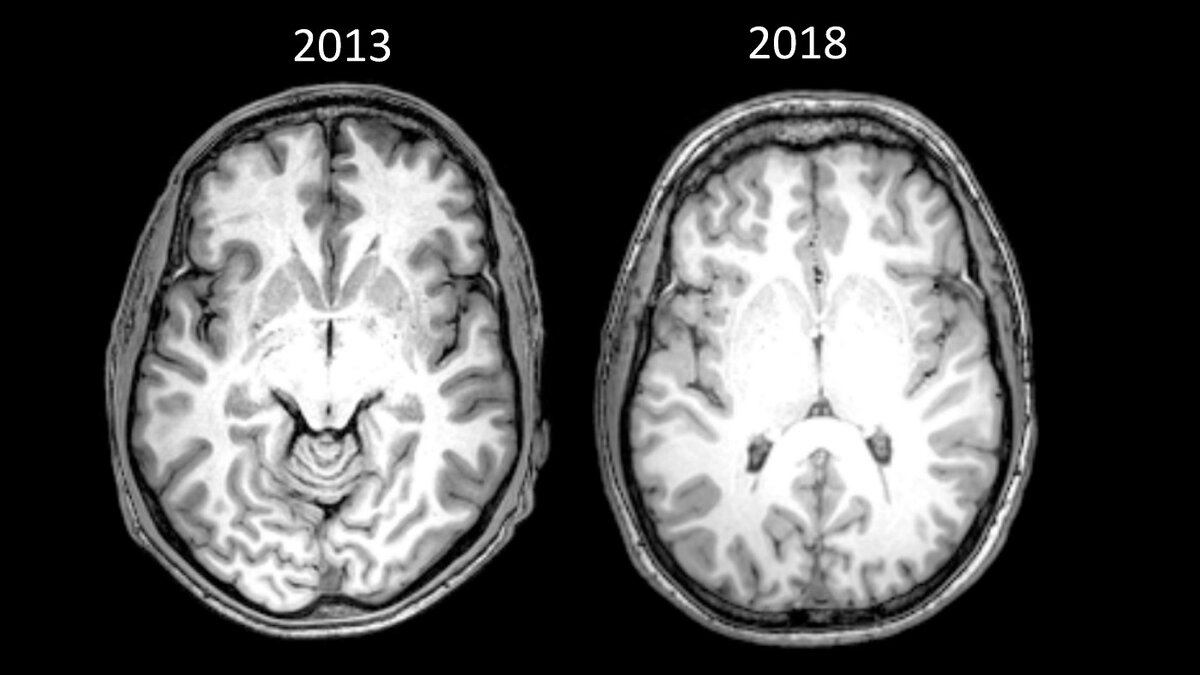

Ниже приведены снимки моего мозга. Левый стал частью исследования, проведённого в 2013 году на второй «чистый» день после 15 лет зависимости. Правый сделан в мае 2018 года, как часть документального фильма о стрессе.

Источник: необработанные снимки моего мозга в 2013 и 2018 годах. Здесь приведён разрез, показывающий переднюю спайку, стандартное анатомическое представление, используемое для сравнения разные сканов мозга. Было сложно сделать прямое сравнение разрезов, потому что использовались разные МРТ, а снимки сделаны в различных разрешениях

Мой мозг так сильно отличался, что человек, который его анализировал, не мог сравнить стандартные визуальные маркеры на глаз (выше привожу более техническое объяснение).

Так же пока сложно понять, что привело к таким разительным изменениям. Между сканами прошло четыре с половиной года, я значительно поменял многие аспекты жизни, включая диету, упражнения и сон. Я вернулся в колледж и, конечно, перестал принимать героин.

Но я сам вижу, что преображение мозга стало следствием того, что я развил чуткость к моменту здесь и сейчас. Всё поменялось, когда мне рассказали об осознанности. Мне дали инструмент, чтобы победить моего злейшего врага — тревожность — это перевернуло игру.